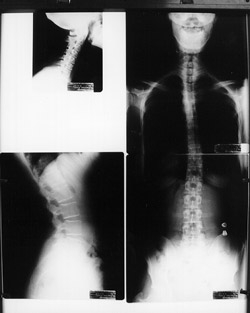

Spinal X-rays may be taken depending on your age, and situation. There are many reasons why we would not take x-rays on certain patients including pregnancy, most children, recent usable spinal x-rays and some other various situations. Aside from these situations, x-rays are a common part of the examination process when looking for vertebral subluxations. X-rays give us important information including the position of the spinal bones, and the quality of the spine and safety of adjusting it. X-rays also tell us the relative length of time subluxations may have been involved in your spine.

With this important information we can make a more accurate determination of the type of adjustments your spine needs as well as the ongoing frequency of your care. Your examination results and x-rays will be explained to you and covered in detail at your Report of Findings. You will be scheduled for your Report of Findings after your initial exam. It is at your Report of Findings that we will give you a care plan and go over any special instructions you will need to obtain the best and fastest possible results, as well as receiving your (or your child's) first adjustment.